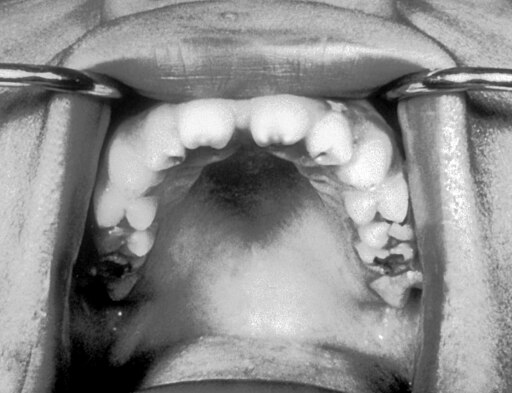

Vrozená syfilis (lues connata, congenita) je onemocnění plodu nebo novorozence získané transplacentárně během těhotenství od infikované matky nebo získané přímým kontaktem s jejími lézemi během porodu.

Vrozená syfilis (kongenitální syfilis, syphilis congenita) je infekce plodu nebo novorozence spirochétou Treponema pallidum získanou od matky intrauterinně (transplacentárně) nebo při porodu. Kongenitální syfilis může být rozdělena do více typů: 1. Infekce matky před početím způsobuje odumření plodu v 5. nebo 6. měsíci těhotenství (luetická infekce plodu před 3. Wikipedie